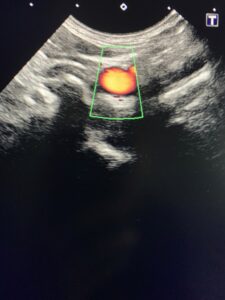

↑↑上の写真は、血管のようなチューブ状のものが見る方向によってどう見えるか?の例です。

←これが血管の横断面。

←そしてこれが同じ血管の縦断面。

同じ血管でも、断面によって見え方が全然違いますね!!

※わかりやすく、血管を赤く色づけしています。